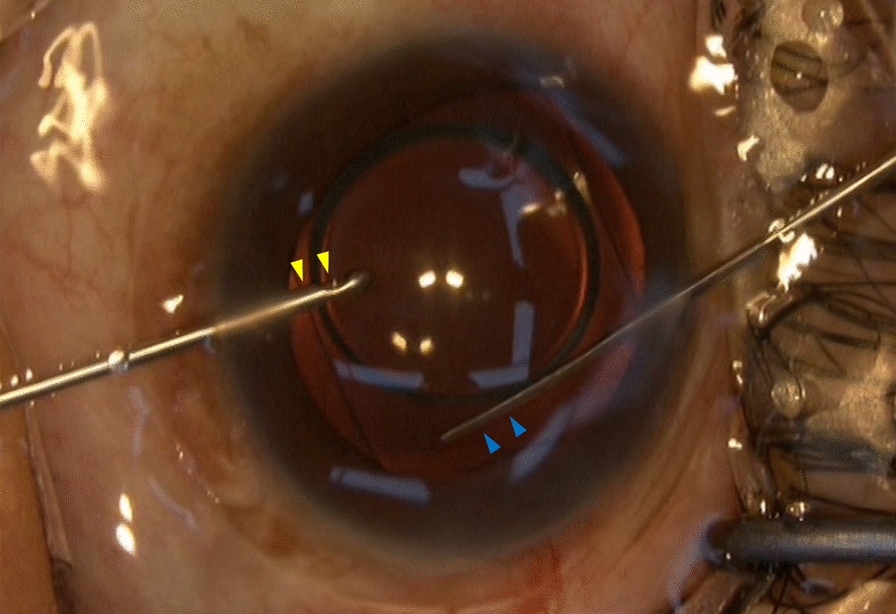

Background: To assess the safety and efficacy of phakic refractive lens (PRL) implantation for correcting high myopia, as well as an ophthalmic viscosurgical device-free (OVD-free) method for PRL implantation.

Methods: In this real-world prospective study, consecutive patients implanted with PRL in one or both eyes were enrolled. Based on the surgical techniques used, the eyes were divided into the OVD-free method group and the conventional method group. The patients were examined 2 h after surgery and were scheduled for follow-up at 1 day, 1 week, 1 month, 3 months, 6 months, and 12 months. The corrected distance visual acuity (CDVA), uncorrected distance visual acuity (UDVA), the manifest refraction spherical equivalent (MRSE), intraocular pressure (IOP) and lens vault were assessed postoperatively. Corneal endothelial cell density (ECD) was measured at the 3- and 12-month postoperative visits.

Results: Fifty-seven consecutive patients (108 eyes) were enrolled. At the 3-month postoperative visit, both mean UDVA and CDVA were significantly improved after PRL implantation (0.19 ± 0.21 and 0.01 ± 0.14 logMAR) with efficacy index and safety index of 0.92 and 1.30, respectively. None of the eyes had any loss of CDVA. The percentage of eyes within ± 0.50 D and ± 1.00 D of target refraction was 58% and 83%, respectively. Mean MRSE changed from - 14.49 ± 4.22 D, preoperatively, to - 1.22 ± 1.26 D at 1 day (P < 0.001) and remained stable thereafter. Mean endothelial cell loss was 11.3%, 9.6%, respectively, at 3 and 12 months, with no significant difference between the two follow-ups (P = 0.395). Fifty-nine eyes received the OVD-free method, and 49 eyes received the conventional method. The OVD-free method demonstrated a significant reduction in the incidence of early acute IOP elevations (28.8% vs. 53.1%, P = 0.022) compared to the conventional method. The difference of initial endothelial cell loss (9.4 ± 14.2% vs. 13.6 ± 14.6%) between the two groups trended toward significance (P = 0.056). In both groups, no other major complications were observed up to 12-month follow-up.

Conclusions: PRL implantation was a safe, efficient, predictable and stable method for correcting high myopia. The potential of lower incidence of early acute IOP elevations makes the OVD-free method a promising alternative to the conventional method.